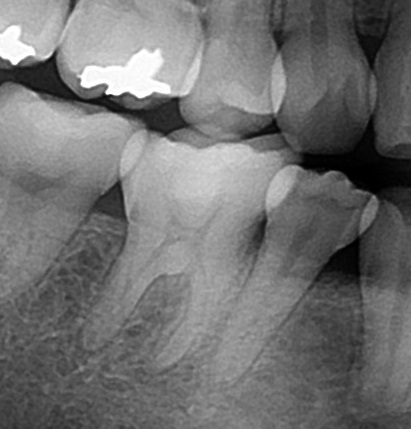

エックス線写真で確認してみると、

このような状態で歯の中が見えます。

レジンは少し白目で写りますので、

ここに詰まっています。

歯の神経は黒く見えますので、

ここに神経が写っています。

照らし合わせてみると、

神経近くの深いところまでレジンが詰めてあるのが確認できます。